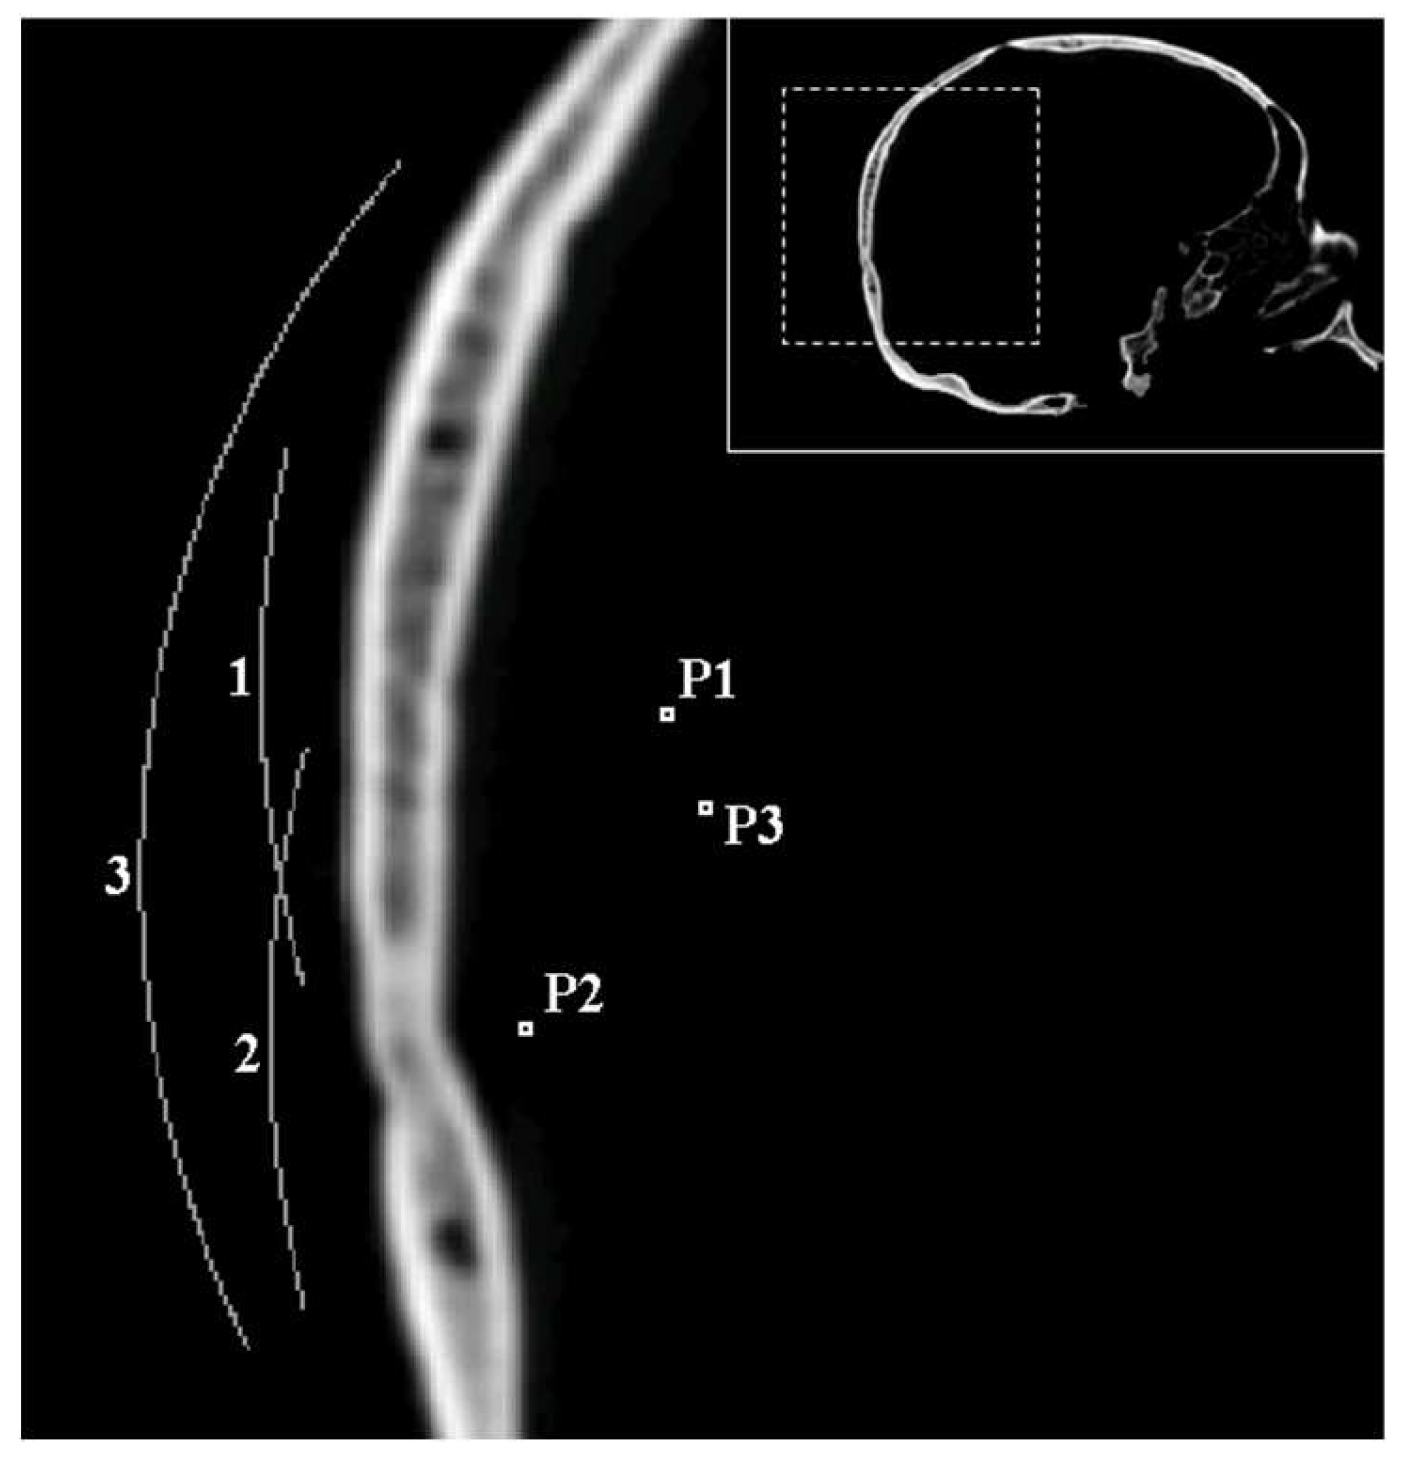

The simulations were carried out with or without the skull interposed between the transducer and target, which were placed at different points (P1, P2, P3), always between the spherical transducer and its geometrical center (Figure 1). At each of these points and for each emitted frequency, we assumed the same protocol, as follows: First of all, the phase pattern was recorded (by means of time reversal simulation from target to transducer) on the holographic recording surface, both with and without the interposed skull. Then, in order to determine the characteristics of the ideal focus, the “gold standard emission”, which consists of emitting from the registration surface affected by the phase pattern recorded without skull, was simulated. Next, a series of six lenses for six different speeds slower than water and another series of six lenses for six speeds faster than water were numerically generated from both the phase patterns recorded with or without the skull. In the graphs and for the sake of brevity, we named concave or convex lenses the lenses produced respectively with fast or slow materials, since all the target points evaluated were located between the lens and its geometric center. The p-wave speeds evaluated ranged from one fourth to four times the wave speed of water.

For each of these simulations, the quality of the −3 and −6 dB focus beams was evaluated attending to seven quantitative indicators described below. The particular values used in the simulation series were the following: The p-wave speeds of the fast lenses were, respectively, 4, 2.5, 1.75, 1.5, 1.375, and 1.3 times the speed of water, whereas the p-wave speeds of the slow lenses were obtained dividing the speed of water by the same series of numbers. The spherical transducers had a radius of 59 mm and an aperture of 64 mm for configuration P3 and 30mm for P1 and P2. Figure 1 shows the target points whose respective distances to the holographic surface were 24.2 mm, 13.8 mm, and 30 mm. In short, there were 96 time forward simulations for the small aperture lens (two types of lens, two frequencies, with and without the skull, two positions, and six speeds) and 13 simulations for the lens of larger aperture.